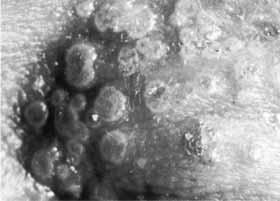

At times, an epithelial lesion may lose its typical configuration to form an ulcer that is usually round and of variable size (Fig. 14). The edges are rolled in appearance and do not contain the “heaped-up” opaque cells that stain brightly with rose bengal typical of a dendritic or geographic herpetic ulcer. Evidence is lacking of viral replication in the epithelium in such indolent, so-called metaherpetic ulcers. However, the electron microscopic picture of Herpesvirus replication may occasionally be demonstrated in indolent ulcers deep in the stroma (Figs. 15 and 16). Often, there is considerable stromal edema or infiltrate associated with these ulcers, or the ulcer may represent breakdown over a previously scarred area. Indolent ulcers are more common in stromal keratouveitis and will be discussed in more detail below.

Fig. 14 Indolent herpetic ulcer. This type of ulcer tends to be circular with smooth, rolled margins that stain poorly, if at all, with rose bengal (see Fig. 15). Electron microscopy revealed Herpesvirus particles in keratocytes at all depths under this ulcer.

Fig. 15 Indolent herpetic ulcer in the same patient as in Fig. 14. Rose bengal stains the base but not the epithelium at the edge of ulcer.